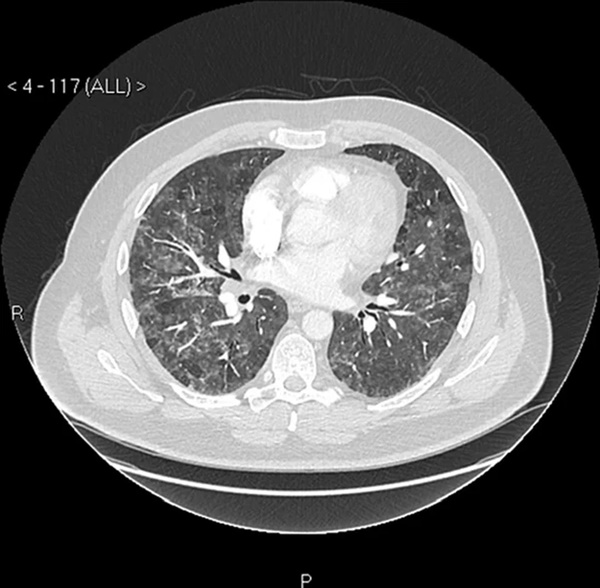

Do không thể chịu nổi tình trạng này nữa, Martin quyết định tới bệnh viện kiểm tra. Qua kết quả chụp X-quang, trên phổi của Martin có nhiều đốm và bác sĩ cảnh báo rằng, anh đang thở một cách rất khó khăn. Tuy nhiên, các bác sĩ vẫn chưa thể tìm ra được vấn đề mà Martin đang gặp phải là gì.

"Sức khỏe của tôi suy giảm rất nhanh, tôi đã tái khám tới 4 lần nhưng đều không nhận được kết quả chẩn đoán chính xác", Martin chia sẻ. Sau nhiều tháng làm xét nghiệm, cuối cùng khi phân tích công thức máu, bác sĩ Owen John Dempsey (Chuyên khoa Lồng ngực tại Bệnh viện BMI Albyn ở Aberdeen) đã tìm ra được nguyên nhân khiến Martin gặp phải tình trạng trên. Kết quả cho thấy, anh đang bị viêm phổi quá mẫn (hậu quả của hen suyễn dị ứng).